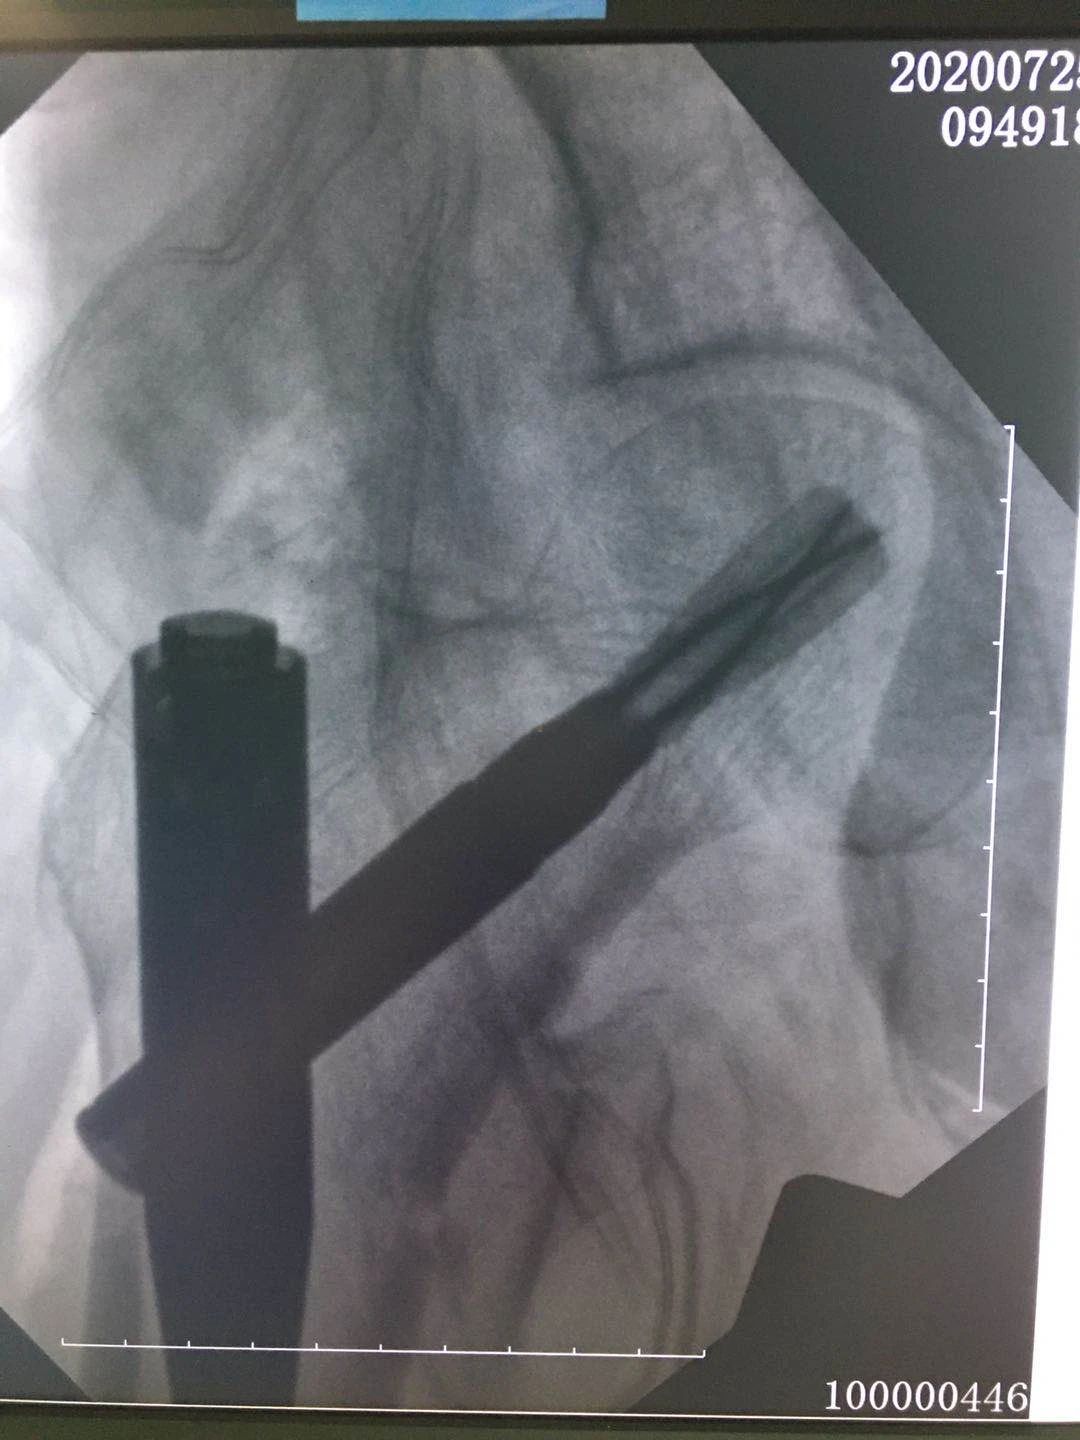

术后影像: